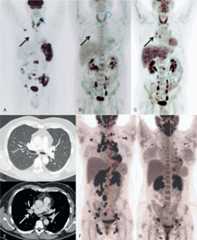

FIGURE 2.

Radiological evolution of lymphoma and sarcoidosis. Positron Emission Tomography/Computerized Tomography (18FDG-PET/CT) of patient 1 at lymphoma diagnosis (A), lymphoma remission after diagnostic splenectomy and chemotherapy (B) and at sarcoidosis diagnosis 2 months later (C). Black arrow indicates the occurrence of moderately hypermetabolic (SUVmax = 3.5) hilar lymphadenopathy at sarcoidosis onset. CT scan at sarcoidosis diagnosis of patient 1 (D and E) shows micronodules in the middle lobe (D) and a 19 mm hilar enlarged lymph node (white arrow, panel E). Panel F and G are18FDG-PET/CT evaluations of patient 2 at sarcoidosis diagnosis (F) and at last follow-up, 6 months after introduction of steroid treatment (panel G) showing a very good PR. PR = partial response, SUV = standardized uptake value.

Overall response to the treatment was good; 12/16 (75%) patients experienced clinical CR. Four patients were classified as nonresponders but the assessment of response to therapy was lacking for 3 of these patients. Six patients had radiological CR, 3 had a PR, and 1 had no radiological response (radiological response was not available for 6 patients) (Figure2). The median duration of corticosteroid treatment was 5.25 months (range, 1–10 months).